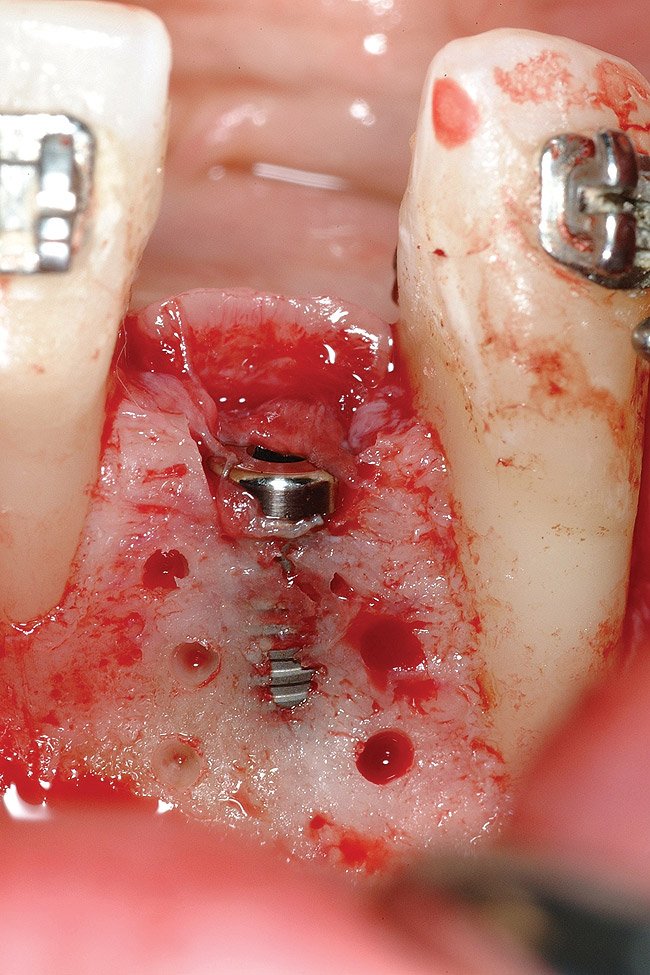

Figure 18   Implant placement with resulting facial dehiscence. Cortical perforations placed to promote angiogenesis.

Figure 18

Figure 19  Mineralized freeze-dried bone allograft hydrated with platelet-derived growth factor covering root dehiscences and implant dehiscence.

Figure 19